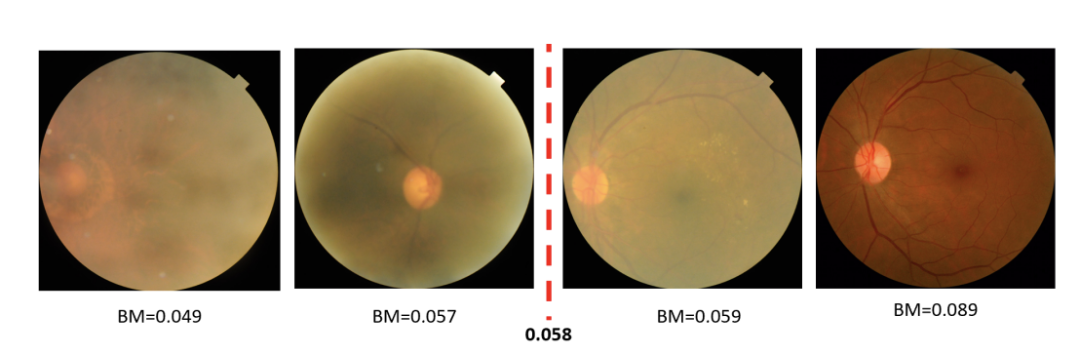

多标签视网膜疾病 (MuReD) 数据集

下载链接:http://ew0bj.avtk.cn/cb

多标签视网膜疾病(MuReD)数据集,使用从三个不同的最先进来源(即 ARIA、STARE 和 RFMiD 数据集)收集的图像,并执行一系列后处理确保图像质量的处理步骤、要分类的广泛疾病以及每个疾病标签有足够数量的样本。MuReD 数据集由 2208 张图像组成,具有 20 个不同的标签,图像质量和分辨率各不相同。同时,确保数据的最低质量,每个标签有足够数量的样本。